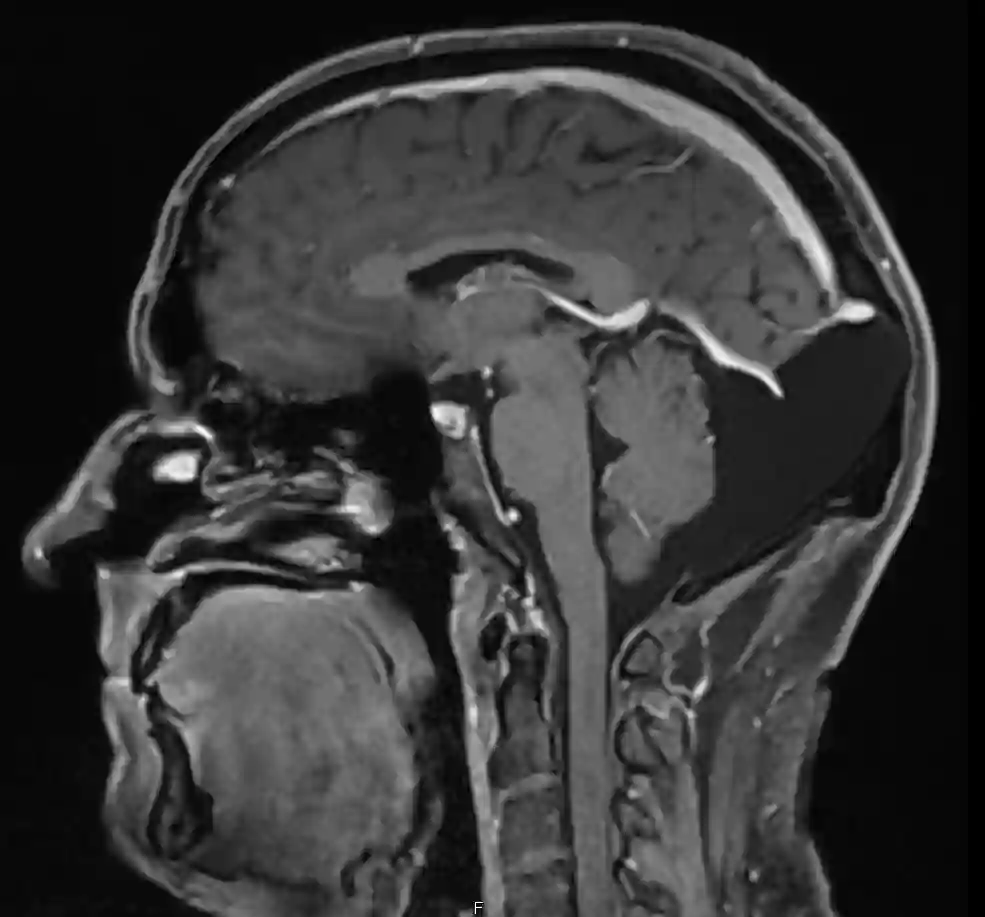

Occipitale Arachnoidalzyste im MRI

Sagittales MRI Bild einer occipitalen Arachnoidalzyste.